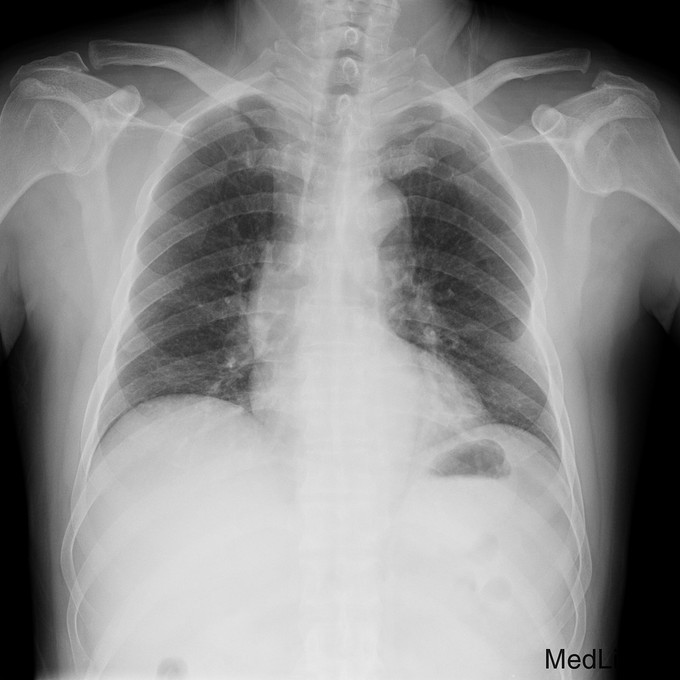

主诉:摔伤后左肩疼痛伴活动受限20天。 病史:患者入院前20天不慎摔伤,左肩不能活动,遂来我院急诊,摄片示左肩锁关节脱位,入院治疗。

查体:左锁骨外端突出,未见明显淤血,局部压痛。